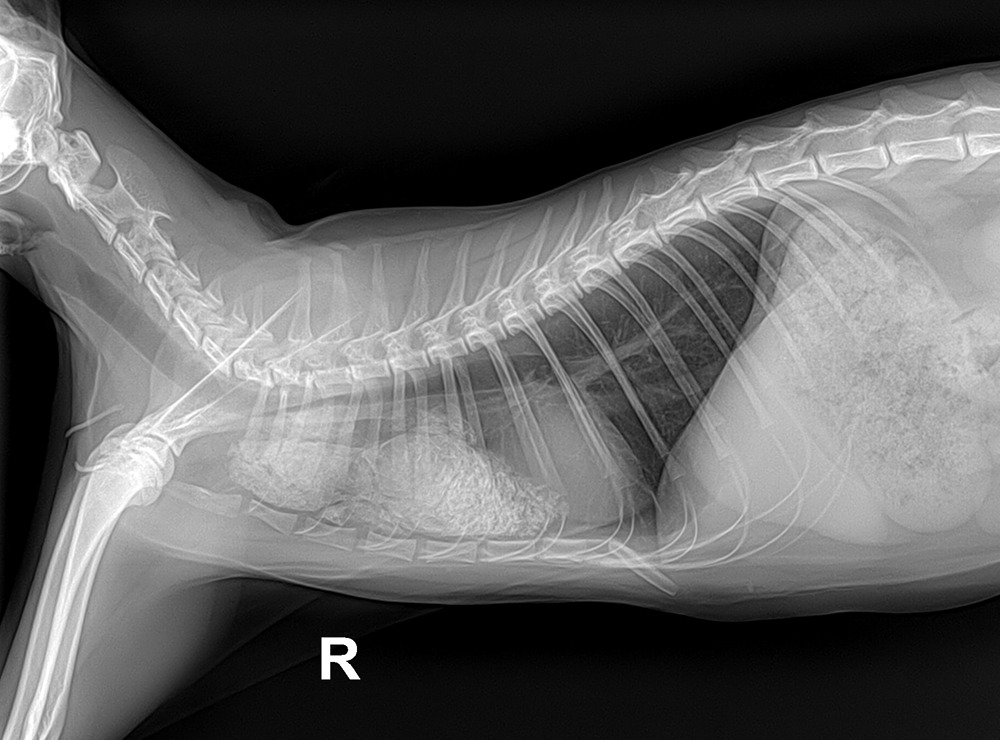

21.jpg 항암치료 21주차의 엑스레이